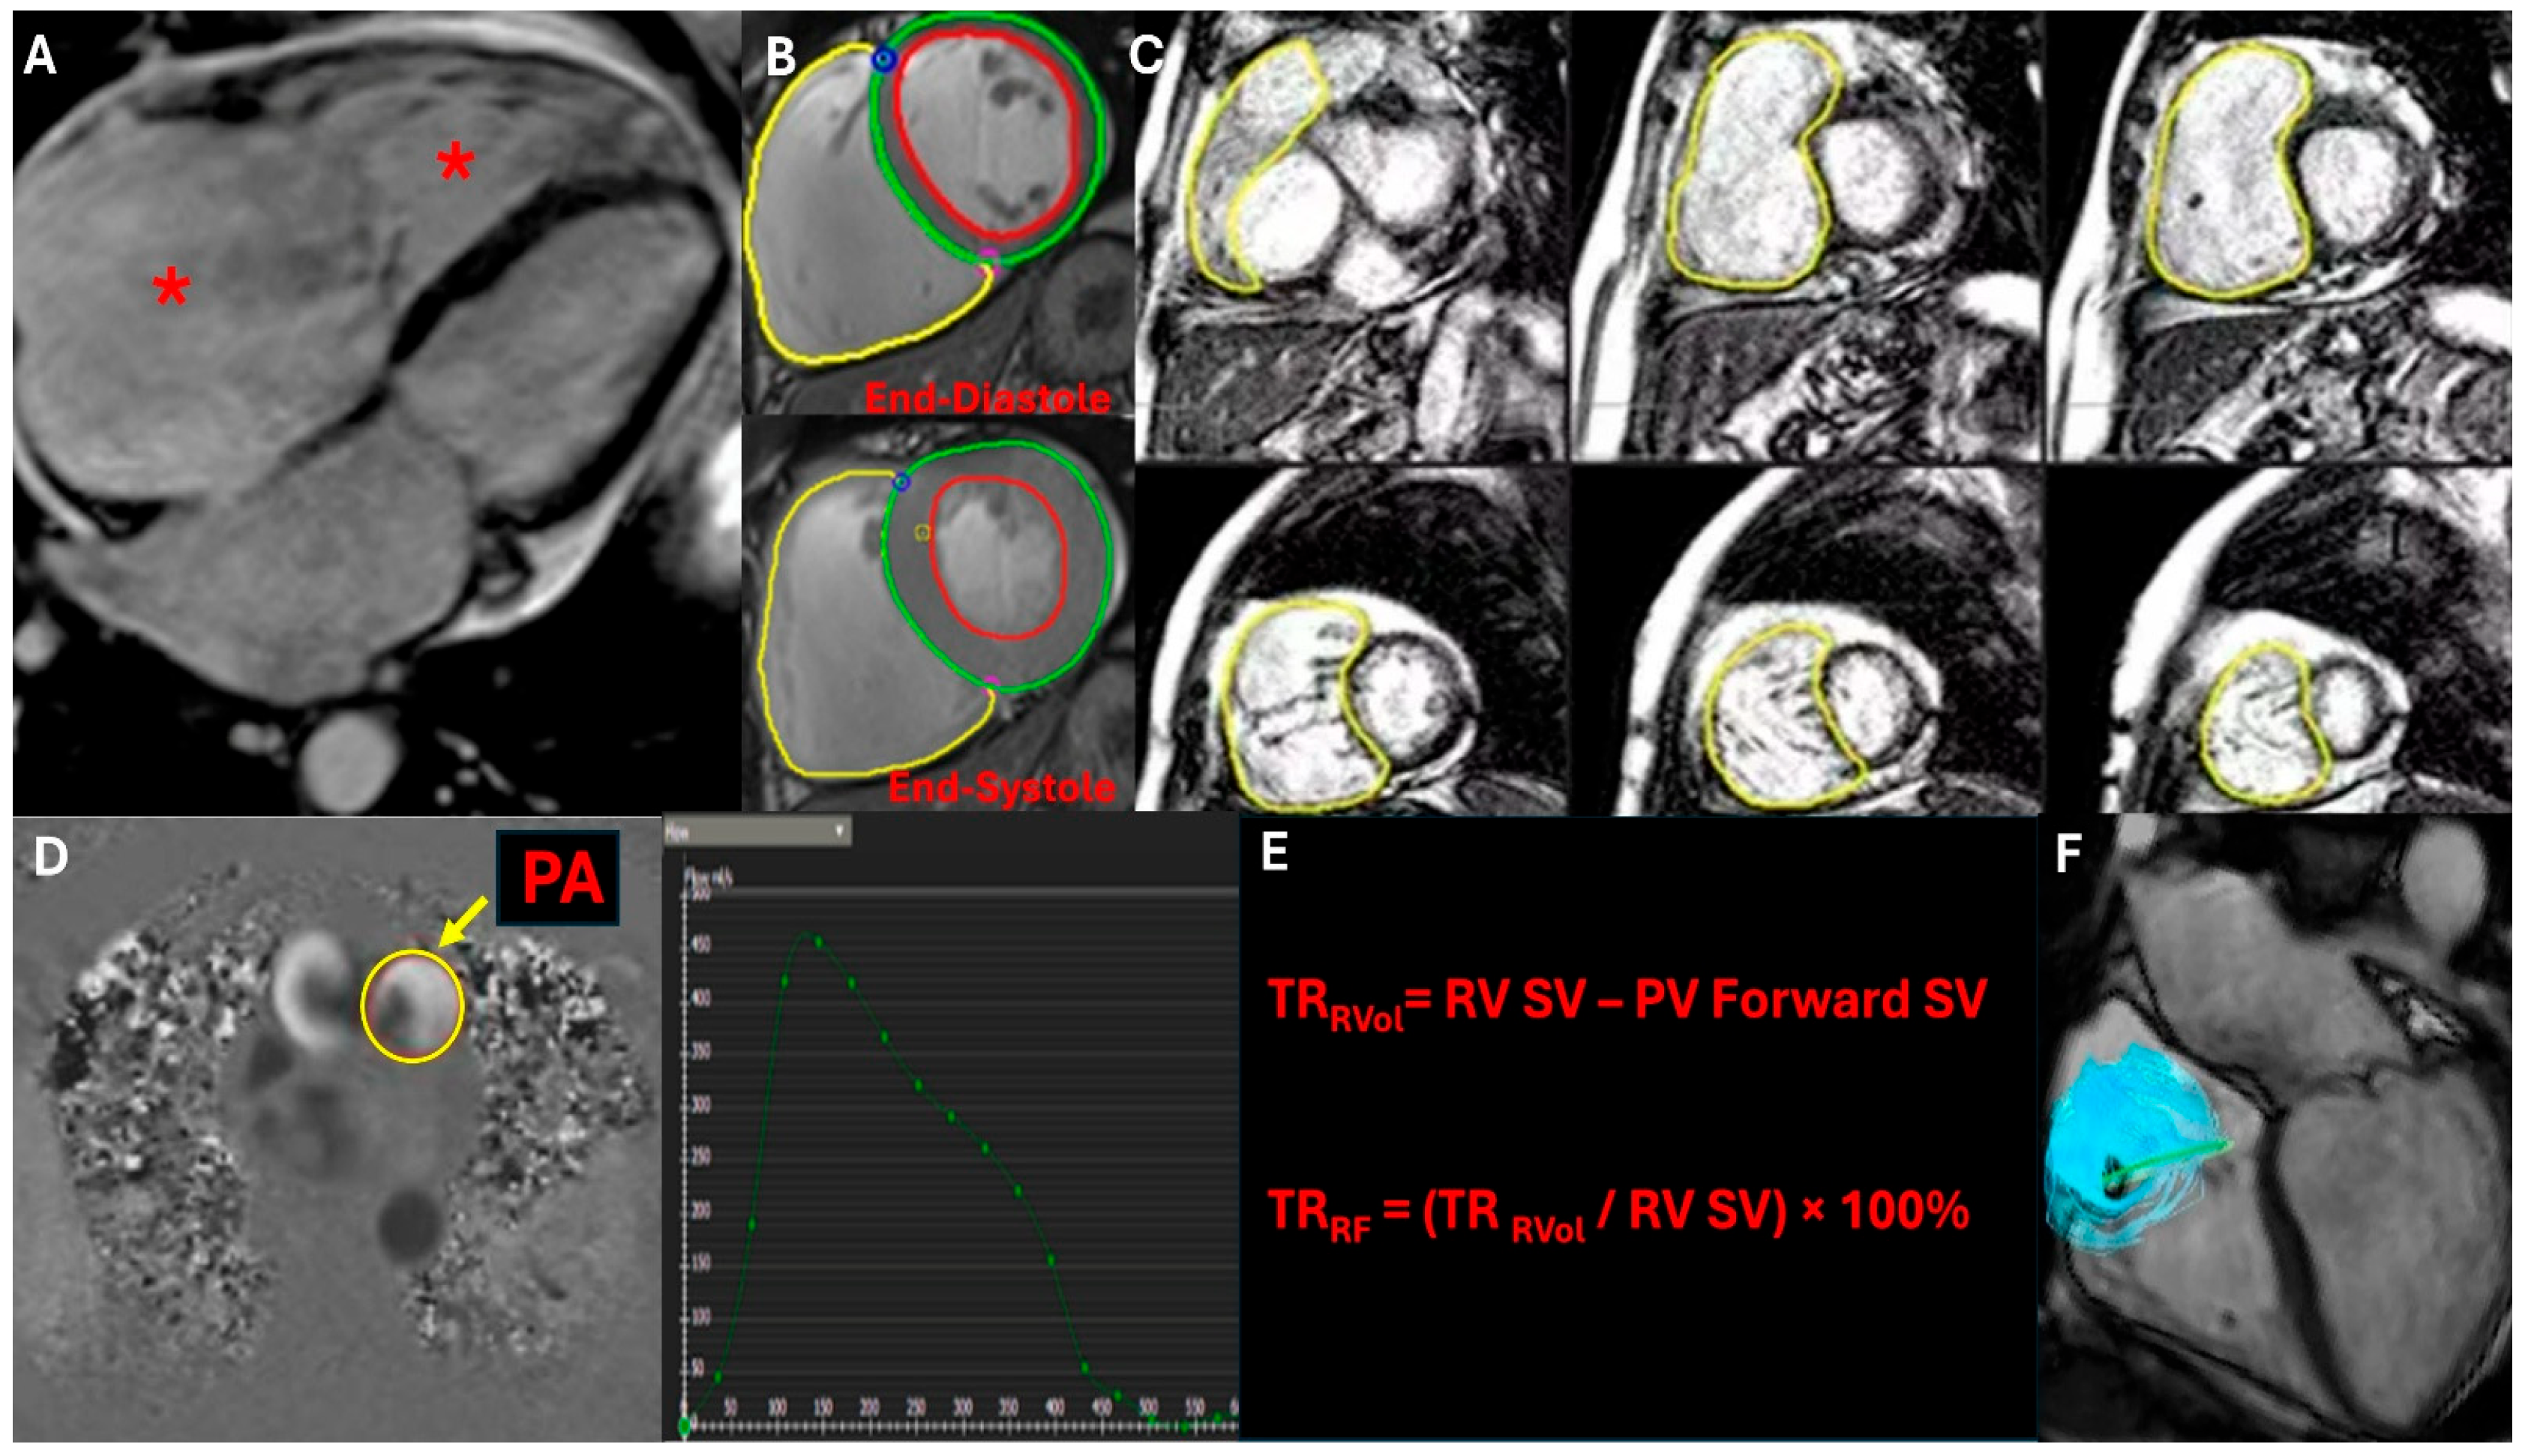

Cardiac magnetic resonance imaging (CMR) is a complementary imaging modality for evaluating isolated TR and assessing RV geometry and function. CMR is generally considered when echocardiographic findings are inconclusive [24]. CMR employs phase-contrast flow imaging to measure forward stroke volume (FSV), defined as the volume of blood ejected through the pulmonic valve, and reverse stroke volume (RSV), representing the volume of blood regurgitated through the tricuspid valve, which enables measurement of regurgitant volume (RV) and regurgitant fraction (RF) across the tricuspid valve. The net stroke volume (NSV), derived from the difference between FSV and RSV, quantitatively assesses TR severity. It also offers a detailed assessment of RV size, morphology, and function, including RV end-diastolic volume, end-systolic volume, and ejection fraction (Figure 4) [25,26]. Additionally, cardiac MRI can evaluate RV myocardial strain, fibrosis, and ventricular remodeling resulting from the long-standing right-sided volume overload. Additionally, CMR allows the detection of pulmonary vascular disorders such as pulmonary hypertension (PH) and other pathologies, such as congenital abnormalities or myocardial diseases. Given its robust reproducibility and non-invasive nature, CMR is increasingly recognized as the gold standard for quantifying right-sided valvular lesions, guiding clinical decision-making and improving risk stratification in patients with moderate to severe TR, and is a promising tool in preoperative/preprocedural planning [24].

Figure 4.

This CMR imaging figure presents a comprehensive assessment of tricuspid regurgitation (TR). (A) Cine four-chamber view showing right atrial (RA) and right ventricular (RV) dilation (red asterisks). (B) Phase-contrast flow imaging capturing the TR jet. (C) 3D whole-heart CMR for RV volumetric assessment, calculating RV end-diastolic volume (RVEDV) and RV end-systolic volume (RVESV). (D) Phase-contrast imaging through the pulmonary artery (PA) to determine pulmonary forward stroke volume (FSV). (E) Quantification of TR severity using regurgitant volume (RVSV-PSV) and regurgitant fraction formulas. (F) 4D flow CMR visualizing TR’s hemodynamic impact through altered flow streamlines.

Figure 4—CMR evaluation of TR (showing RV quantification, TR qualitative, and pulmonic flow and formula)

A retrospective study at the Cleveland Clinic Foundation investigated the prognostic value of echocardiography and CMR in patients with isolated severe TR [25]. Among 262 patients (21% with primary TR), 33.2% underwent tricuspid valve surgery after CMR. Over a mean follow-up of 2.5 years, 26.0% of patients died. CMR-derived TR fraction (HR: 1.15 per 5% increase) and echocardiography-derived right ventricle free wall longitudinal strain (HR: 1.10 per 1% decrease in magnitude) were independently associated with worse survival, along with right heart failure symptoms (HR: 2.03). Tricuspid valve surgery showed borderline protective effects (HR: 0.55). Optimal thresholds for mortality prediction included a regurgitant fraction ≥ 30%, regurgitant volume ≥ 35 mL, and RV free wall longitudinal strain ≥ −11% [25].